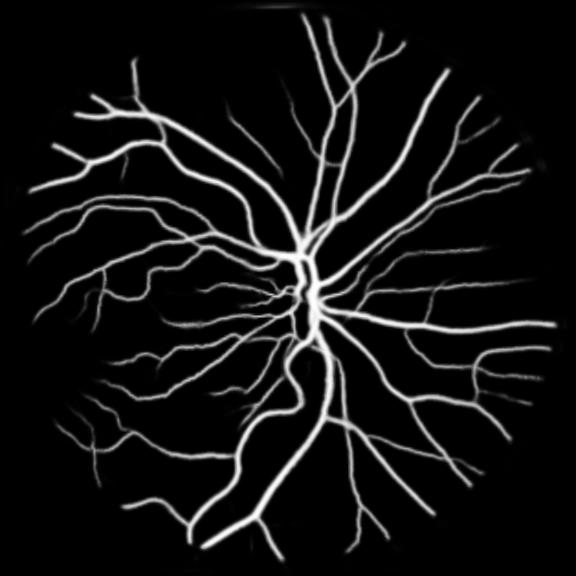

All three datasets are processed by subtracting the mean and normalizing according to the standard deviation. We use Adam optimizer, set the initial learning rate to 0.001 which is reduced by ten times if the training set loss does not drop during 10 consecutive epochs. We augment data using rotation, crop, flip, shift, change in contrast, brightness and hue. We set batch size to 4 for Skin Dataset and 32 for DRIVE and CHASE_DB1 whose patch size is relatively smaller. For each model we train 50 epochs and the result is shown in Table 1. Models with MixModule have better performance than those not and the best performance in each metric all comes from MixModule-based models. We also show some outputs of the networks in Figure 4.